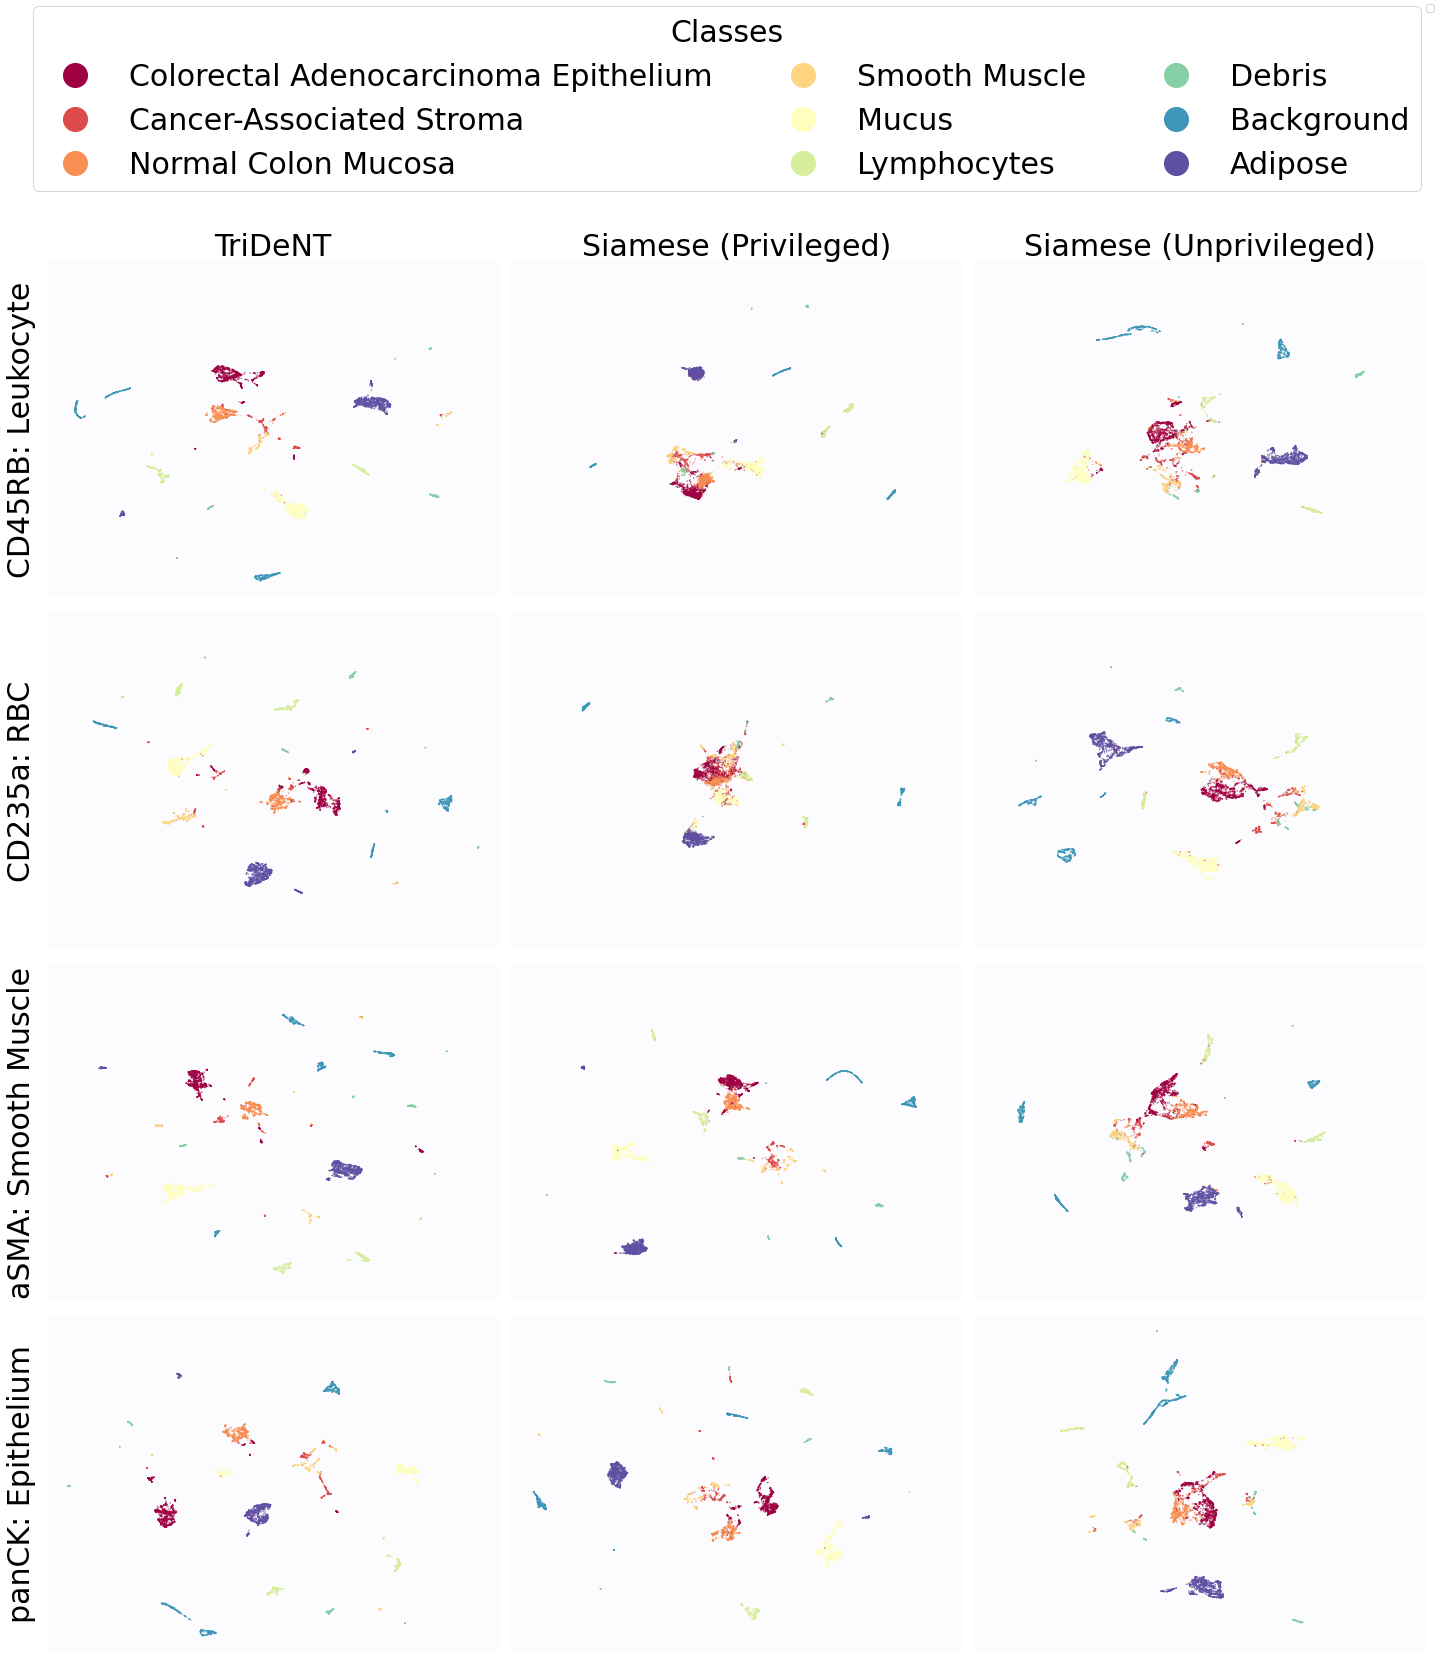

To further analyse the learned representations, we produce UMAP projections of the latent space labelled with the tissue types for the NCT tissue type classification task, as shown for CD3CD20 and SMA in Figure 4(a), and for all SegPath stains in Figures S8 and S9. These figures make the reasons for the varying performance of the privileged Siamese model more apparent. For stains with better performing privileged Siamese models, such as SMA, the UMAPs are very similar between Siamese methods and TriDeNT, with well-differentiated tissue type clusters. In those with worse performance, such as ERG, the tissue types are poorly differentiated, often with only adipose and background forming distinct clusters from the other classes. On closer inspection, it is notable in these projections that TriDeNT ♆ produces more well-defined and separated clusters in general than Siamese networks. This is further evidenced in Figure S7, where TriDeNT ♆ is shown to identify clusters with overexpression of a given gene significantly more effectively than an unprivileged Siamese model.